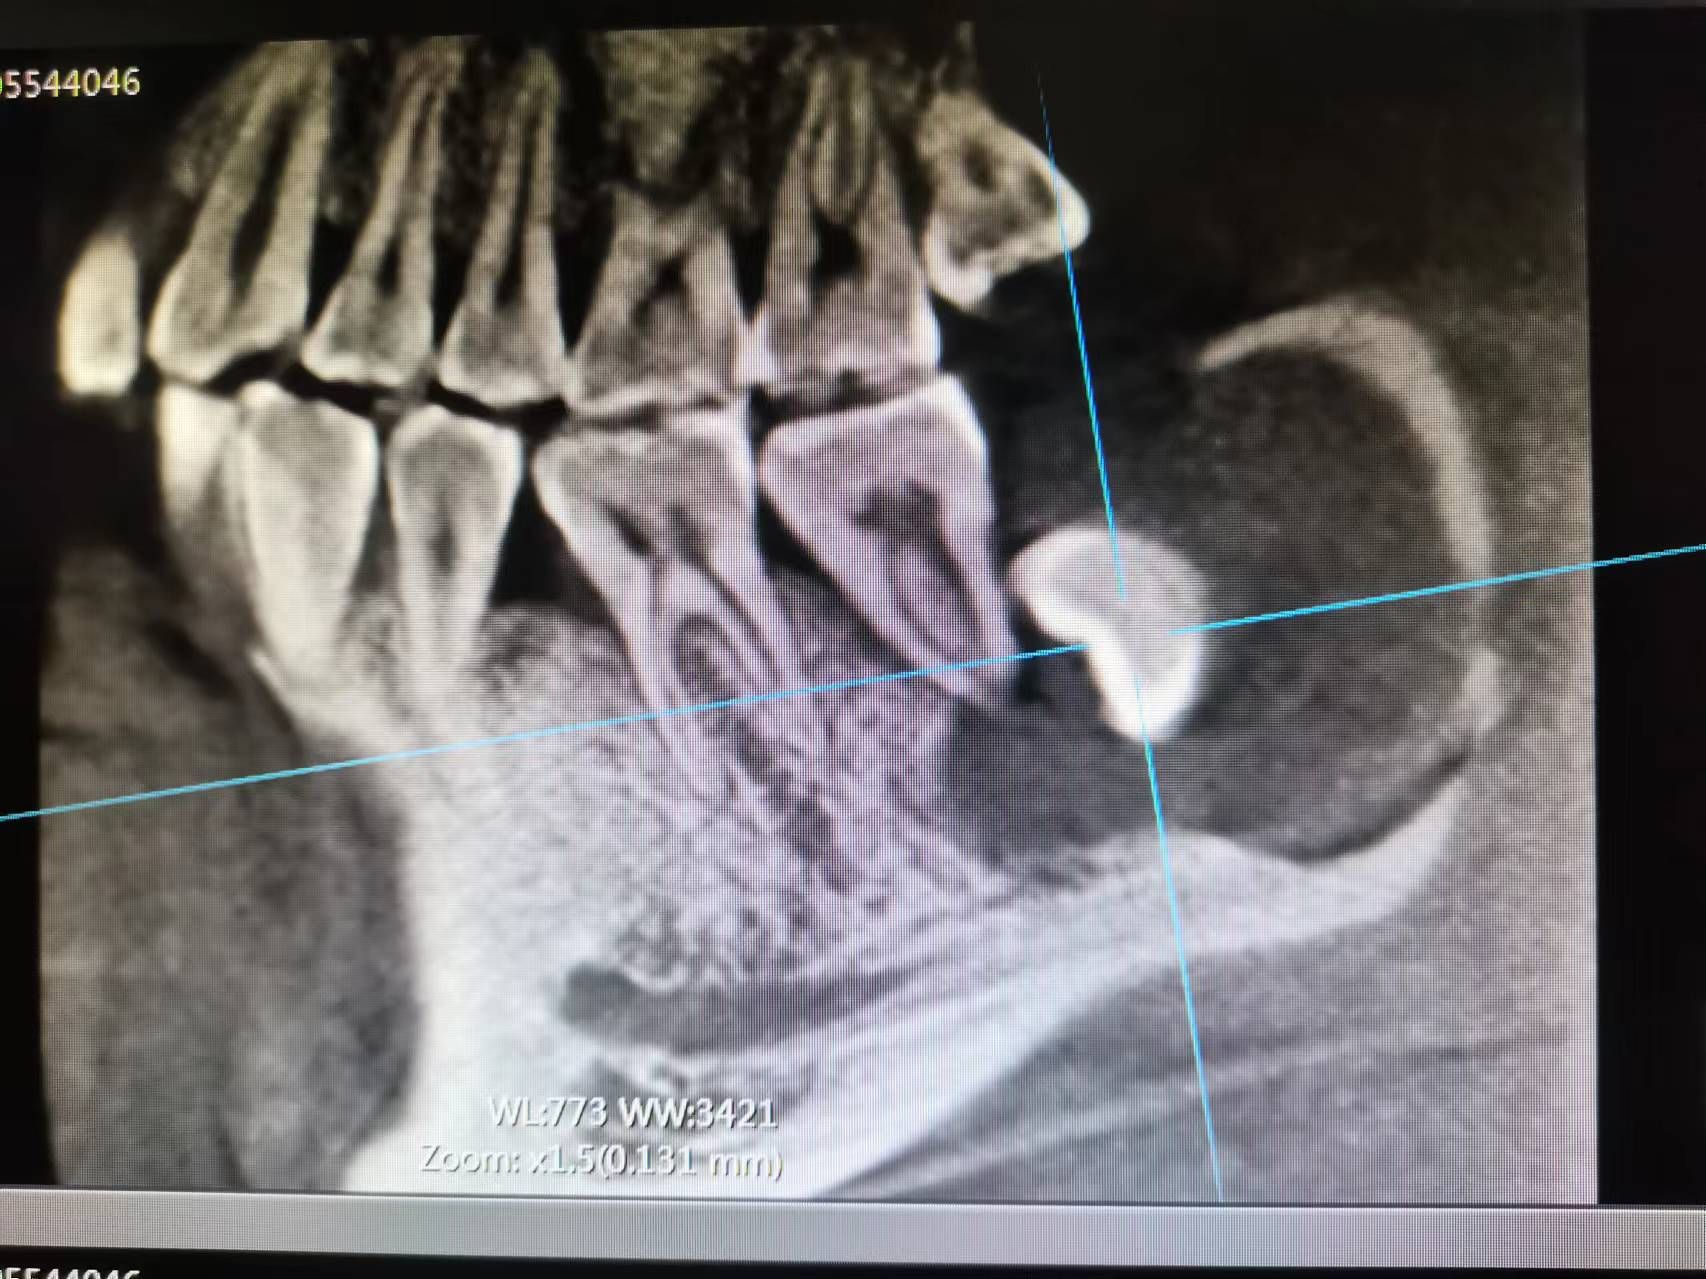

患者张先生2个月前突然发现,自己下颌左侧牙齿,遇凉、热都会剧烈疼痛,甚至不敢用左侧牙齿吃东西,在某口腔门诊钻开牙齿,反复换药治疗几次后仍未见缓解,才想着到大医院看一看。二一五医院口腔科接诊后发现,患者口内下颌最后一颗牙齿上有溢出的白色充填材料,而这颗患牙在几次不当治疗后,已经明显松动,且咬合时剧烈疼痛,患者自述在前期治疗过程中没拍X线片明确病情,接诊医师随即为他安排了口腔CT拍摄。CT发现,在这“摇摇欲坠”的牙齿下,还悄悄隐藏着一颗倾斜的智齿,而这颗智齿,已经几乎“吃光了”它侧方“松动”牙齿的牙根,这才是导致张先生牙疼反复治疗无效的根本原因!